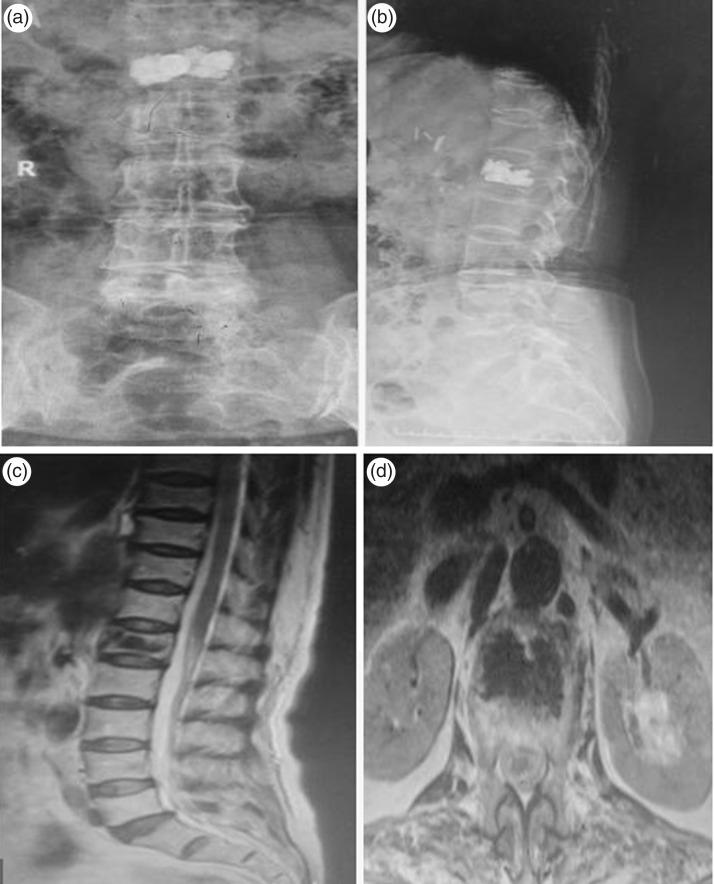

Patients with thoracolumbar OVCFs were recruited and randomly divided into three treatment groups: PCVP, unilateral percutaneous vertebroplasty (PVP) or bilateral PVP. Bone cement dispersion in the fractured vertebrae was observed. Surgery duration, X-ray frequency, bone cement injection volume, bone cement leakage rate and visual analogue scale (VAS) scores were recorded.

Among 78 patients included, surgery duration and X-ray frequency were significantly lower in the PCVP and unilateral PVP groups versus bilateral PVP group. Bone cement injection volume was significantly higher in the bilateral PVP group (6.3 ± 1.4 ml) versus unilateral PVP (3.5 ± 1.1 ml) and PCVP groups (4.6 ± 1.2 ml). VAS scores at 24 h and 3 months post-surgery were significantly decreased versus baseline in all groups. The bone cement leakage rate was lowest in the PCVP group (8.8% [3/34 patients]).

PCVP is associated with reduced trauma, less complicated surgery with shorter duration, fewer X-rays, lower complication rate, and quicker postoperative recovery versus unilateral and bilateral PVP.